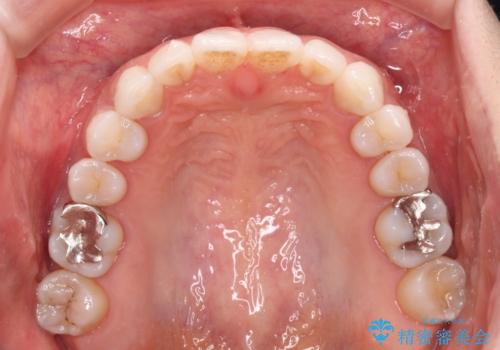

- 前歯のデコボコを気にして来院された患者様です。

歯列不正が軽度であり、インビザラインの装着時間を遵守してくださったため、日本と海外を行き来しながらも2年弱でしっかりと仕上げることができました。